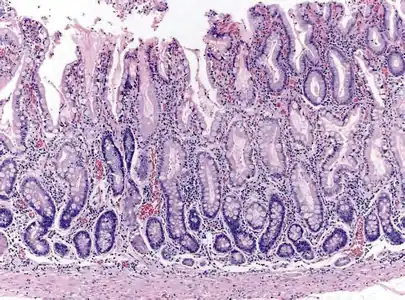

Histopathology of antral mucosa with atrophy. H&E 10x. Antral gastric mucosa with accentuated atrophy because replacement by extensive intestinal metaplasia.